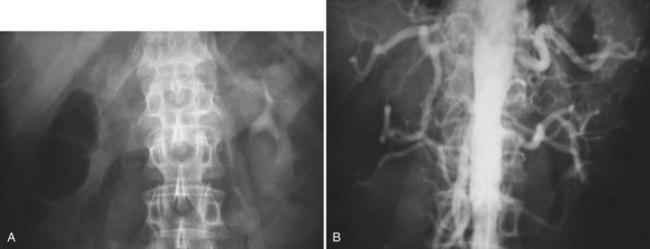

Figure 54–5 Arterial anatomy can be well defined using CT (A) and three-dimensional reconstruction (B).

Frequent anatomic variation in the renal vasculature contributes to the complexity of open renal surgery. Multiple renal arteries, which typically arise from the aorta or iliac arteries, are the most common variation, occurring in 25% to 30% of the population (Merklin and Michels, 1958; Boijsen, 1959; April, 1997). Supernumerary hilar renal arteries originate at the aorta adjacent to the renal artery and traverse the renal hilum, whereas polar renal arteries originate at a greater distance from the main renal artery and enter the renal parenchyma directly. Ectopic and horseshoe kidneys more frequently have supernumerary renal arteries (Fig. 54–11).

Figure 54–11 Horseshoe kidney with multiple arterial branches well defined with three-dimensional imaging.

Modern imaging permits a thorough anatomic evaluation of the urinary tract before open renal surgery. It is essential to identify anatomic variants before surgery such as supernumerary renal arteries, retroaortic left renal vein, circumaortic renal vein, duplicated collecting system, and renal ectopia. A variety of imaging modalities are available, including intravenous pyelography, retrograde pyelography, ureteroscopy, computed tomography (CT), ultrasonography, magnetic resonance imaging (MRI), renal arteriography, and renal venography.

Three-dimensional (3D) volume-rendered CT is a valuable tool in the evaluation of patients undergoing renal surgery (Coll et al, 1999; Derweesh et al, 2003). CT can demonstrate vital information including the anatomy of the renal vasculature, orientation of the kidney, and characteristics of renal tumors, including location, depth of penetration into the kidney, relationship with collecting system, and segmental arterial supply to the tumor (Coll et al, 1999) (Figs. 54-12 to 54-14). CT is also able to characterize other surgically relevant processes, including renal arterial disease, nephrolithiasis, and hydroureteronephrosis (Herts, 2005).